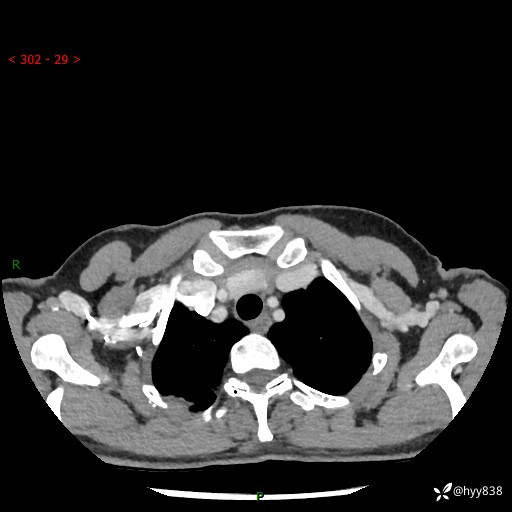

胸部CT平扫